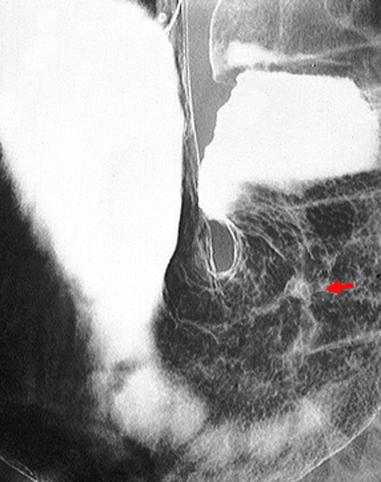

症例提示(所在地,施設名等): 愛知県・ 愛知県がんセンター

TIC症例

疾患(病理主体)の分類悪性上皮性腫瘍/腺癌

部位(臓器別)胃(部位)/2つ以上

検査方法X-P

腫瘍の肉眼分類4型(びまん浸潤型)/

病変の最大径(ミリ)40以上

腫瘍の深達度ss(a1)

多発腫瘍(同一臓器)